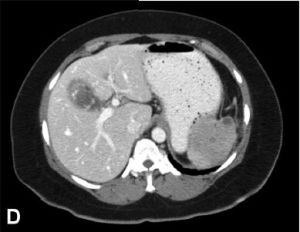

3.CT掃描對腹膜後膿腫的診斷和定位具有極大幫助,其敏感性可達100%,尤其對多發性膿腫的診斷再次手術入路的選擇和手術範圍的確定具有特殊重要的意義。